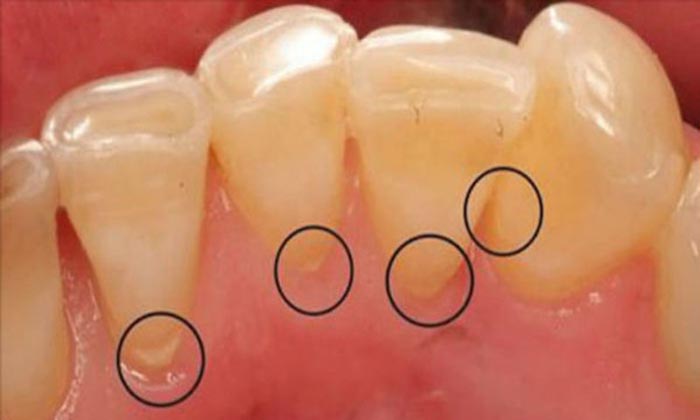

- Reduz e previne a acumulação de placa, cáries e gengivite

O óleo de coco combate as bactérias que existem por exemplo nas pastilhas que mascamos, e que corroem o esmalte dentário, e criam acumulação de cálcio, que é a origem de muitas infecções e de cáries. Não só vai reduzir drasticamente a probabilidade de vir a ter gengivite ou problemas mais sérios ainda, tais como o cancro da boca, e também elimina o mau hálito.